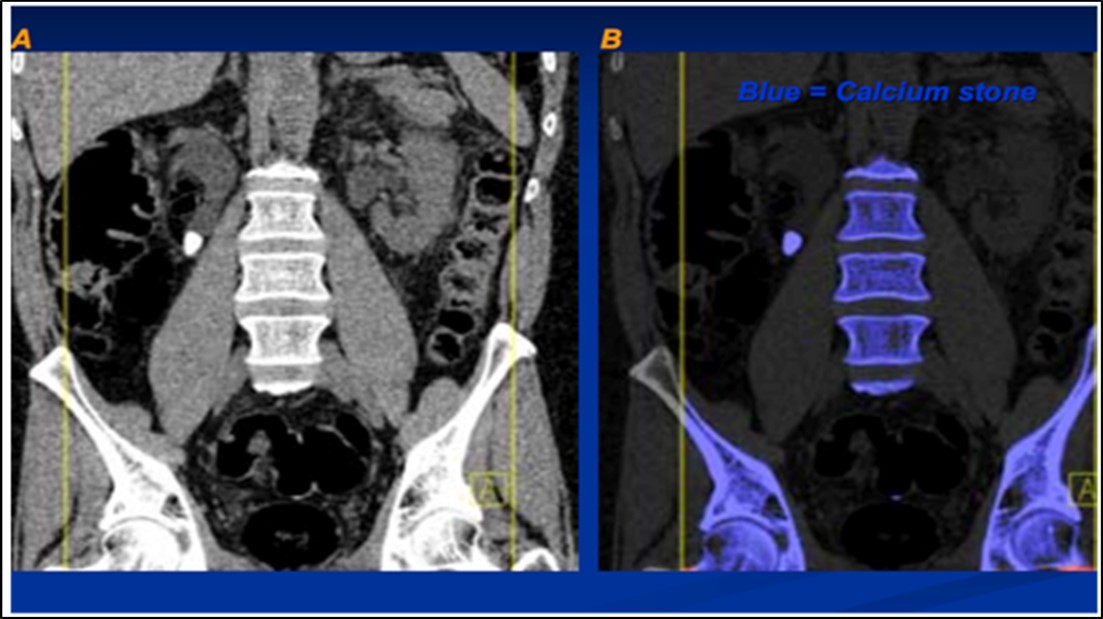

The attenuation difference is shown in colors. In graph 1, the 1.15 ratio represents threshold between uric acid and other stones. If a data point corresponding to a stone with unknown composition falls below this line, the algorithm will characterize such stone as a UA stone and will assign it a predefined red color. And if it falls above the line it will be identified as a non-UA stone and will be shown blue 2.

Stone analysis, together with serum and 24-hour urine metabolic evaluation, can identify the etiology in more than 95% of patients 1. Preoperative prediction of stone type (figure 1 and figure 2) is crucial for therapeutic decision making and follow-up 2, 3, 4, 5, 6. Some studies have reported predictive role of dual energy CT scan for determination of stone type 7, 8, 9.